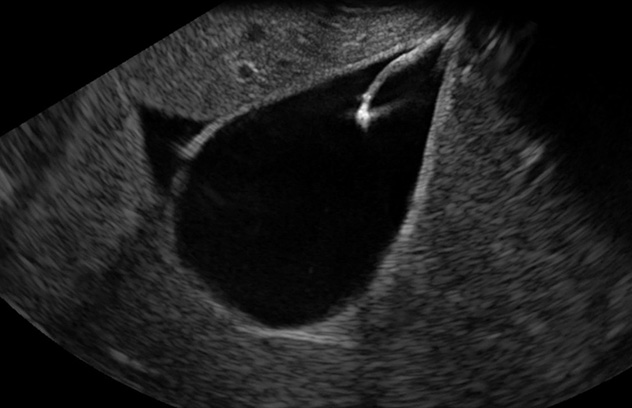

This image shows a large tissue resection in the stomach using a magnet traction device.

Our goal in this project is to develop techniques that allow for resection of large polyps and select early cancers through the endoscope that were previously not amenable to conventional endoscopic techniques. We're developing a new magnet traction device for use in a resection technique that is safe, efficient and easy to use.